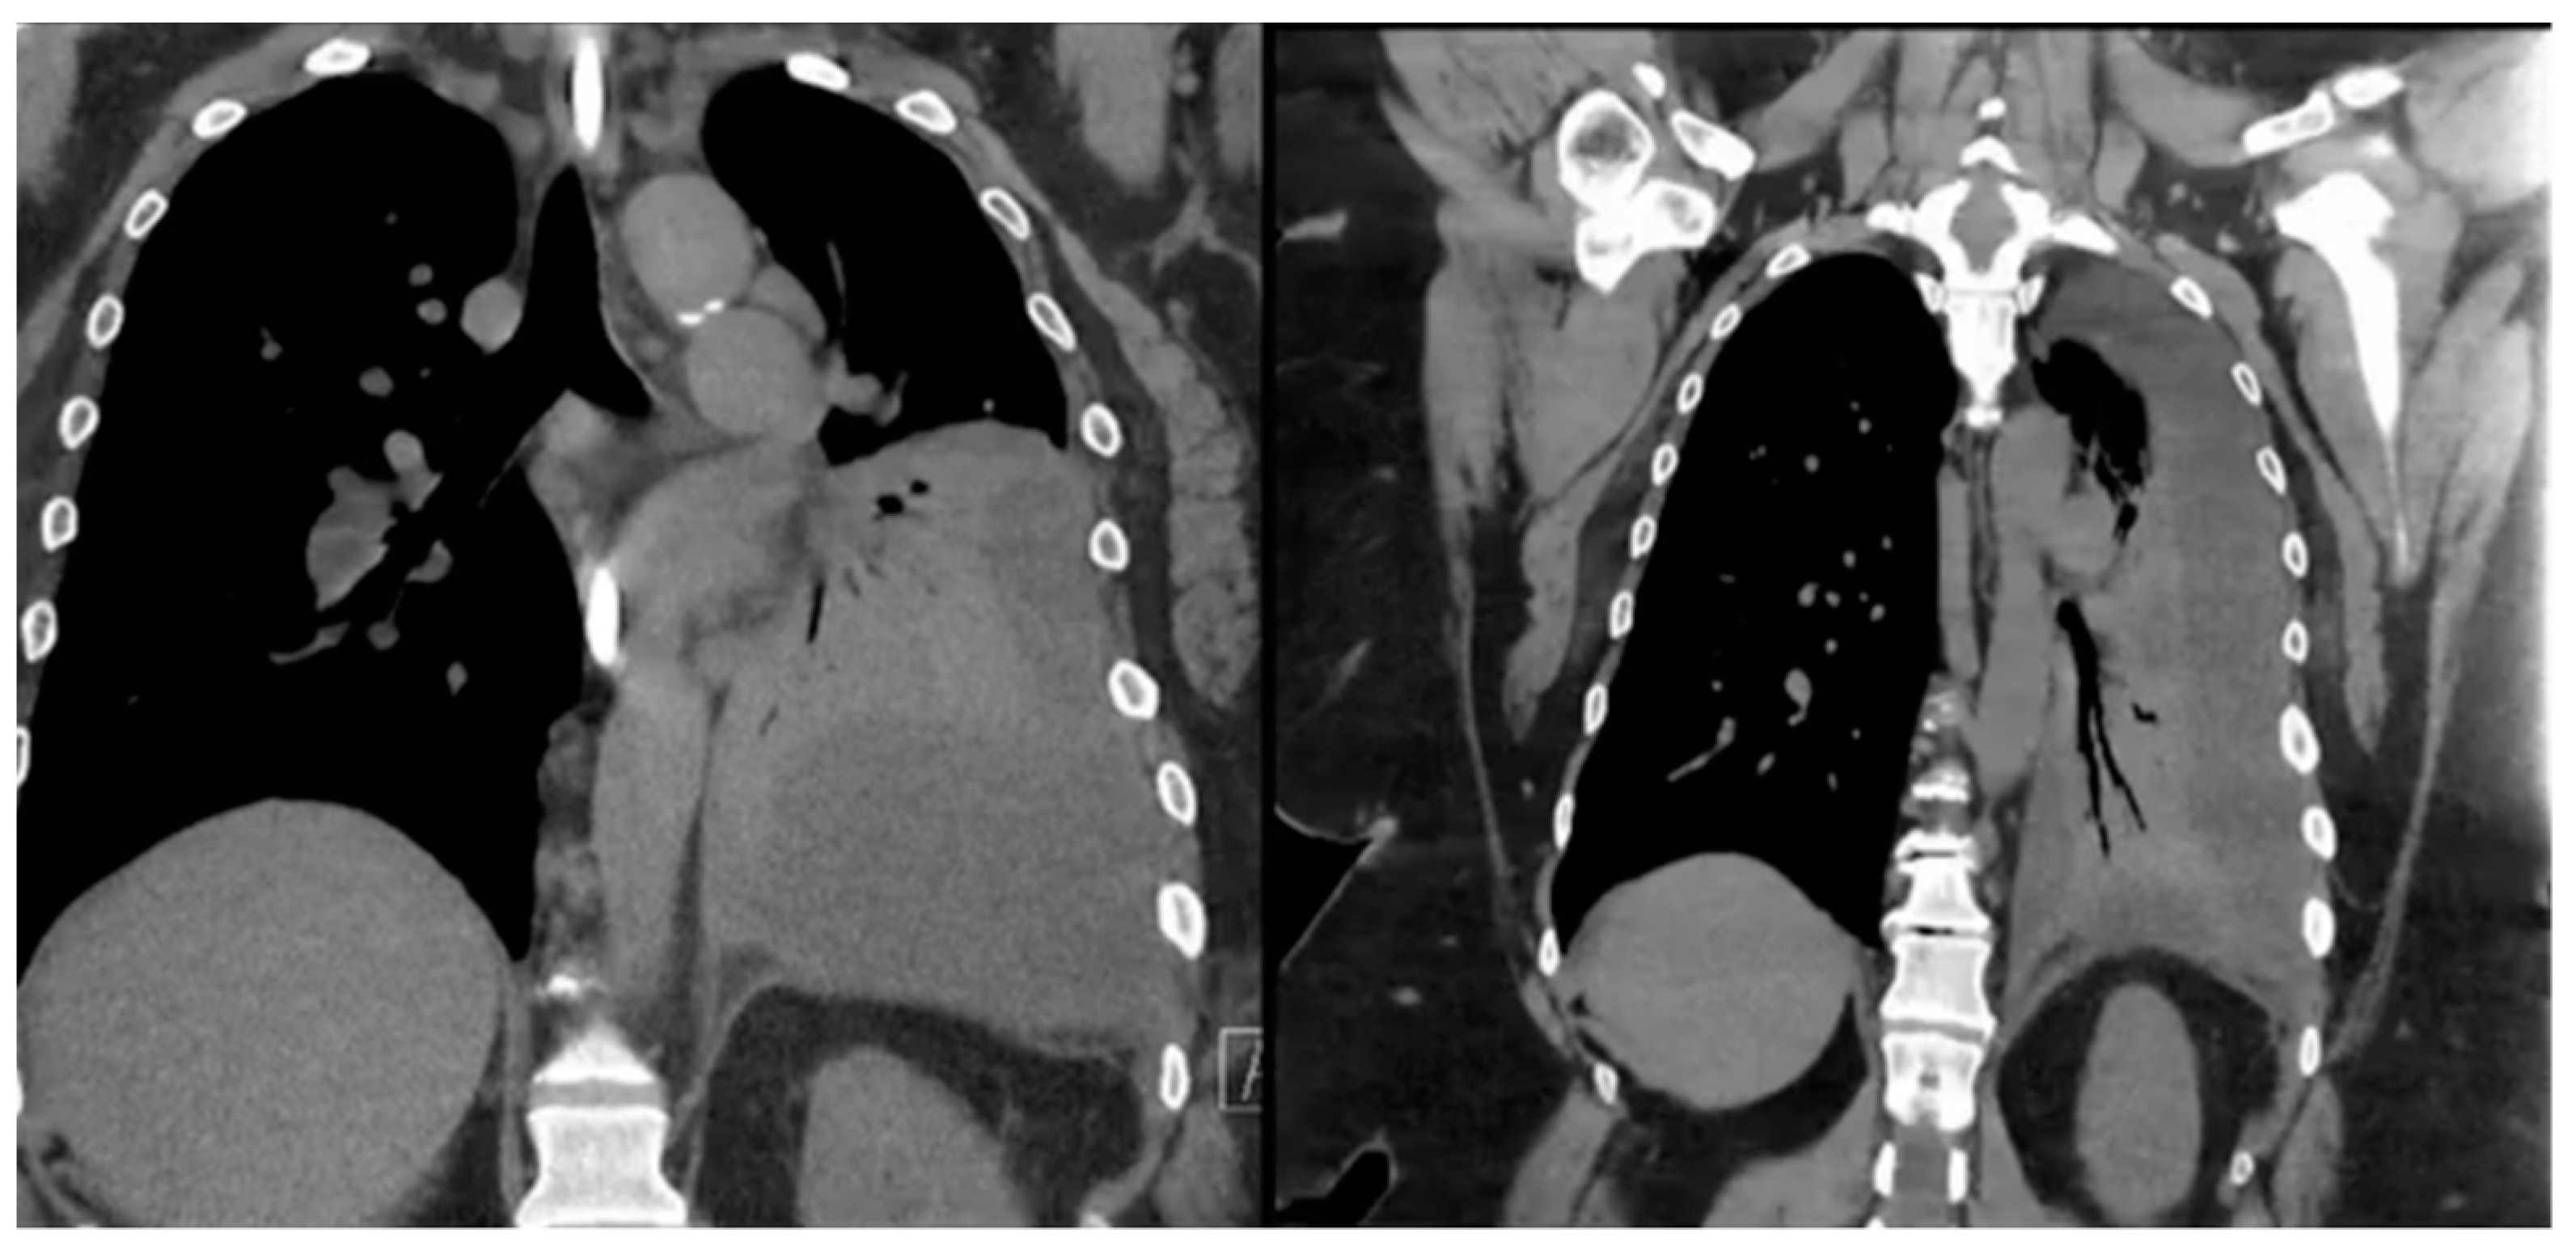

11. Portomesenteric Venous Thrombosis (PMVT)